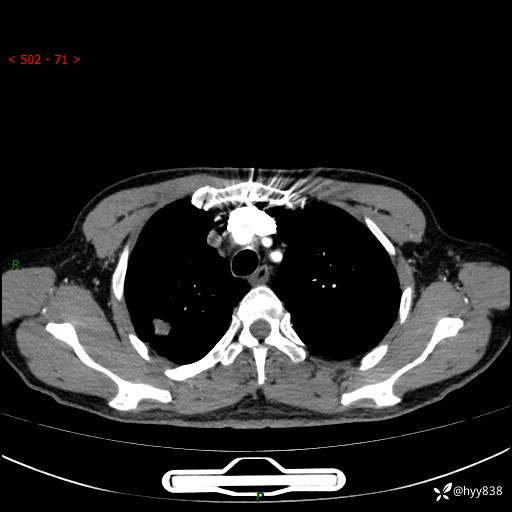

69岁/男,发现肺部病变6天。该有的征象都有,肉芽肿 VS 肿瘤,一念之间---(有结果)

主诉:发现肺部病变6天。

现病史:患者6天前于我院泌尿外科住院,住院期间行胸部CT检查,提示“肺部病变”,患者无畏寒、发热、盗汗、咳嗽、咳痰、咯血、胸痛、呼吸困难,无反酸、腹痛、腹泻、头痛、头晕等不适。未予特殊处理,现为进一步诊治,门诊以“肺肿物”收入我科。 患者本次起病以来,精神食欲尚可,大小便正常,体力及体重无明显变化。

胸部CT平扫+增强